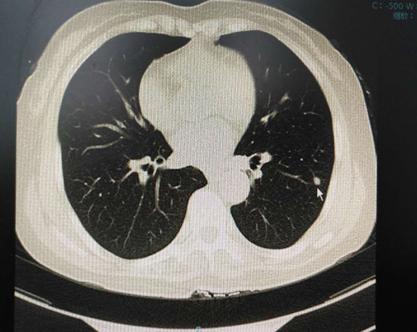

王女士,48岁,半年前当地检查ct发现左肺结节,无明显症状,当时医生嘱3~6个月复查,后来我院查ct,影像及报告见下图

问症状,患者仅有微咳嗽,胸闷,舌质淡,苔薄白,脉弦细。考虑为寒痰凝结,温化寒痰治疗一个月后查ct,影像及报告见下图:

结节明显变小,前方继续加减治疗2个月,停药半个月,复查查ct,影像及报告见下图,结节基本消失。